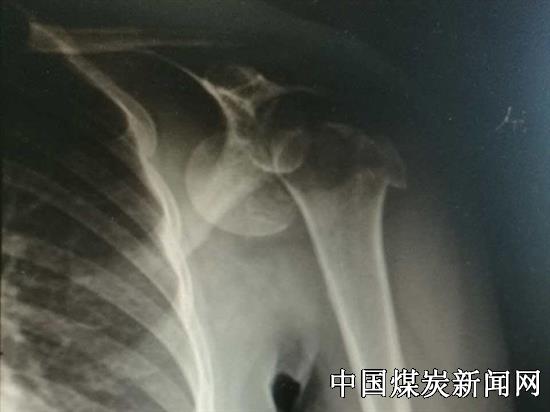

46岁的女性患者陈某,因摔伤后导致左肩部疼痛、肿胀,肩部不能活动,经过X线片检查显示其肱骨头粉碎性骨折并脱位,该院骨六科主治医师郭家全具有丰富的关节创伤治疗经验,受伤的患者预约请他治疗,入住总医院骨六科,在该科主任牛志强大力支持和指导下他积极准备手术器械,认真制定手术计划。对此病例,考虑患者肱骨头粉碎性骨折,大家讨论认为若常规行内固定易失效,且易发生严重并发症,影响肩关节康复,最后决定为其行肩关节置换术。